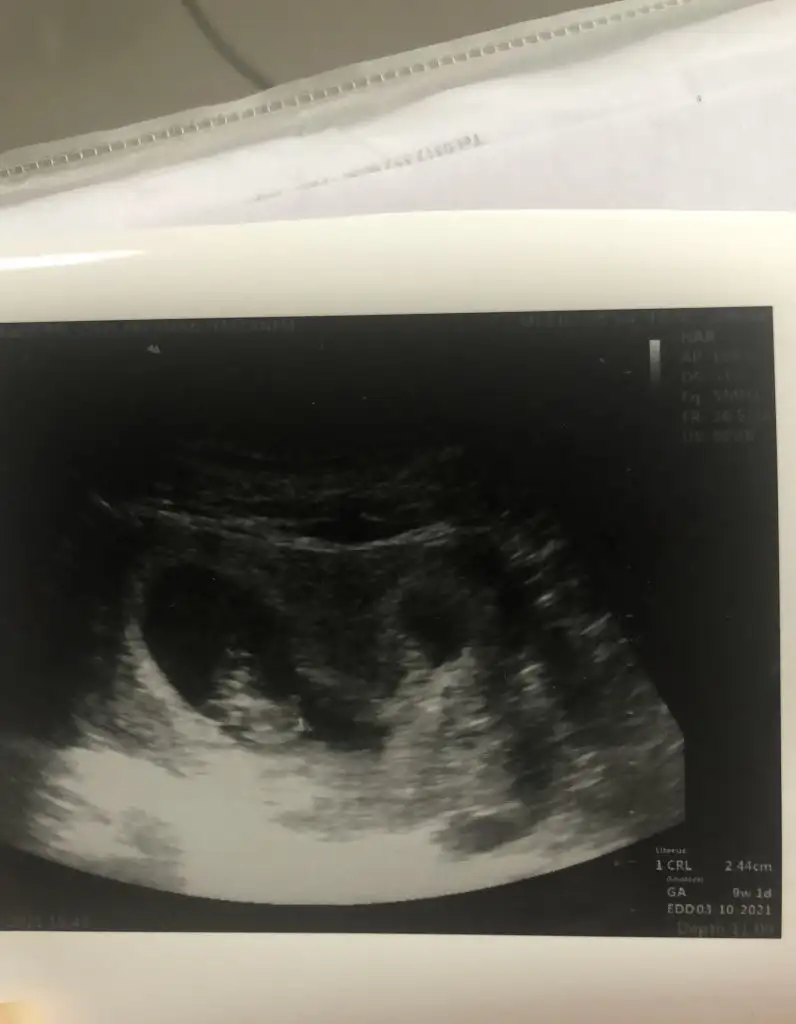

Kiz benceEki Görüntüle 2787858 12+1den görüntü tahmin yaparsanız sevinirim doktor bi tahminde bulundu fakat merak ettim

Hımm doktor erkek gibi demişti tabi her şey olabilirKiz bence